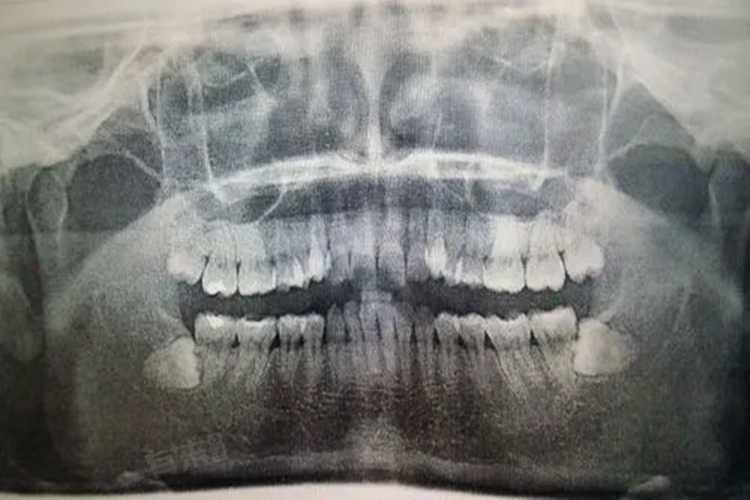

- 横着长的智齿,也称为阻生智齿,虽然在当下可能没有明显的疼痛症状,但却存在潜在的危害。阻生智齿往往会对相邻的牙齿造成挤压,这种挤压力量可能会逐渐导致邻牙的牙根吸收,破坏邻牙的结构完整性,更容易发生龋坏,严重情况下甚至会导致邻牙松动、脱落。

- 阻生智齿还有可能造成牙列拥挤,正常的牙齿排列会因为阻生智齿的存在而被打乱,影响正常的咬合关系。咬合不正常会进而影响咀嚼功能,使得食物无法被充分咀嚼,加重胃肠道的消化负担。